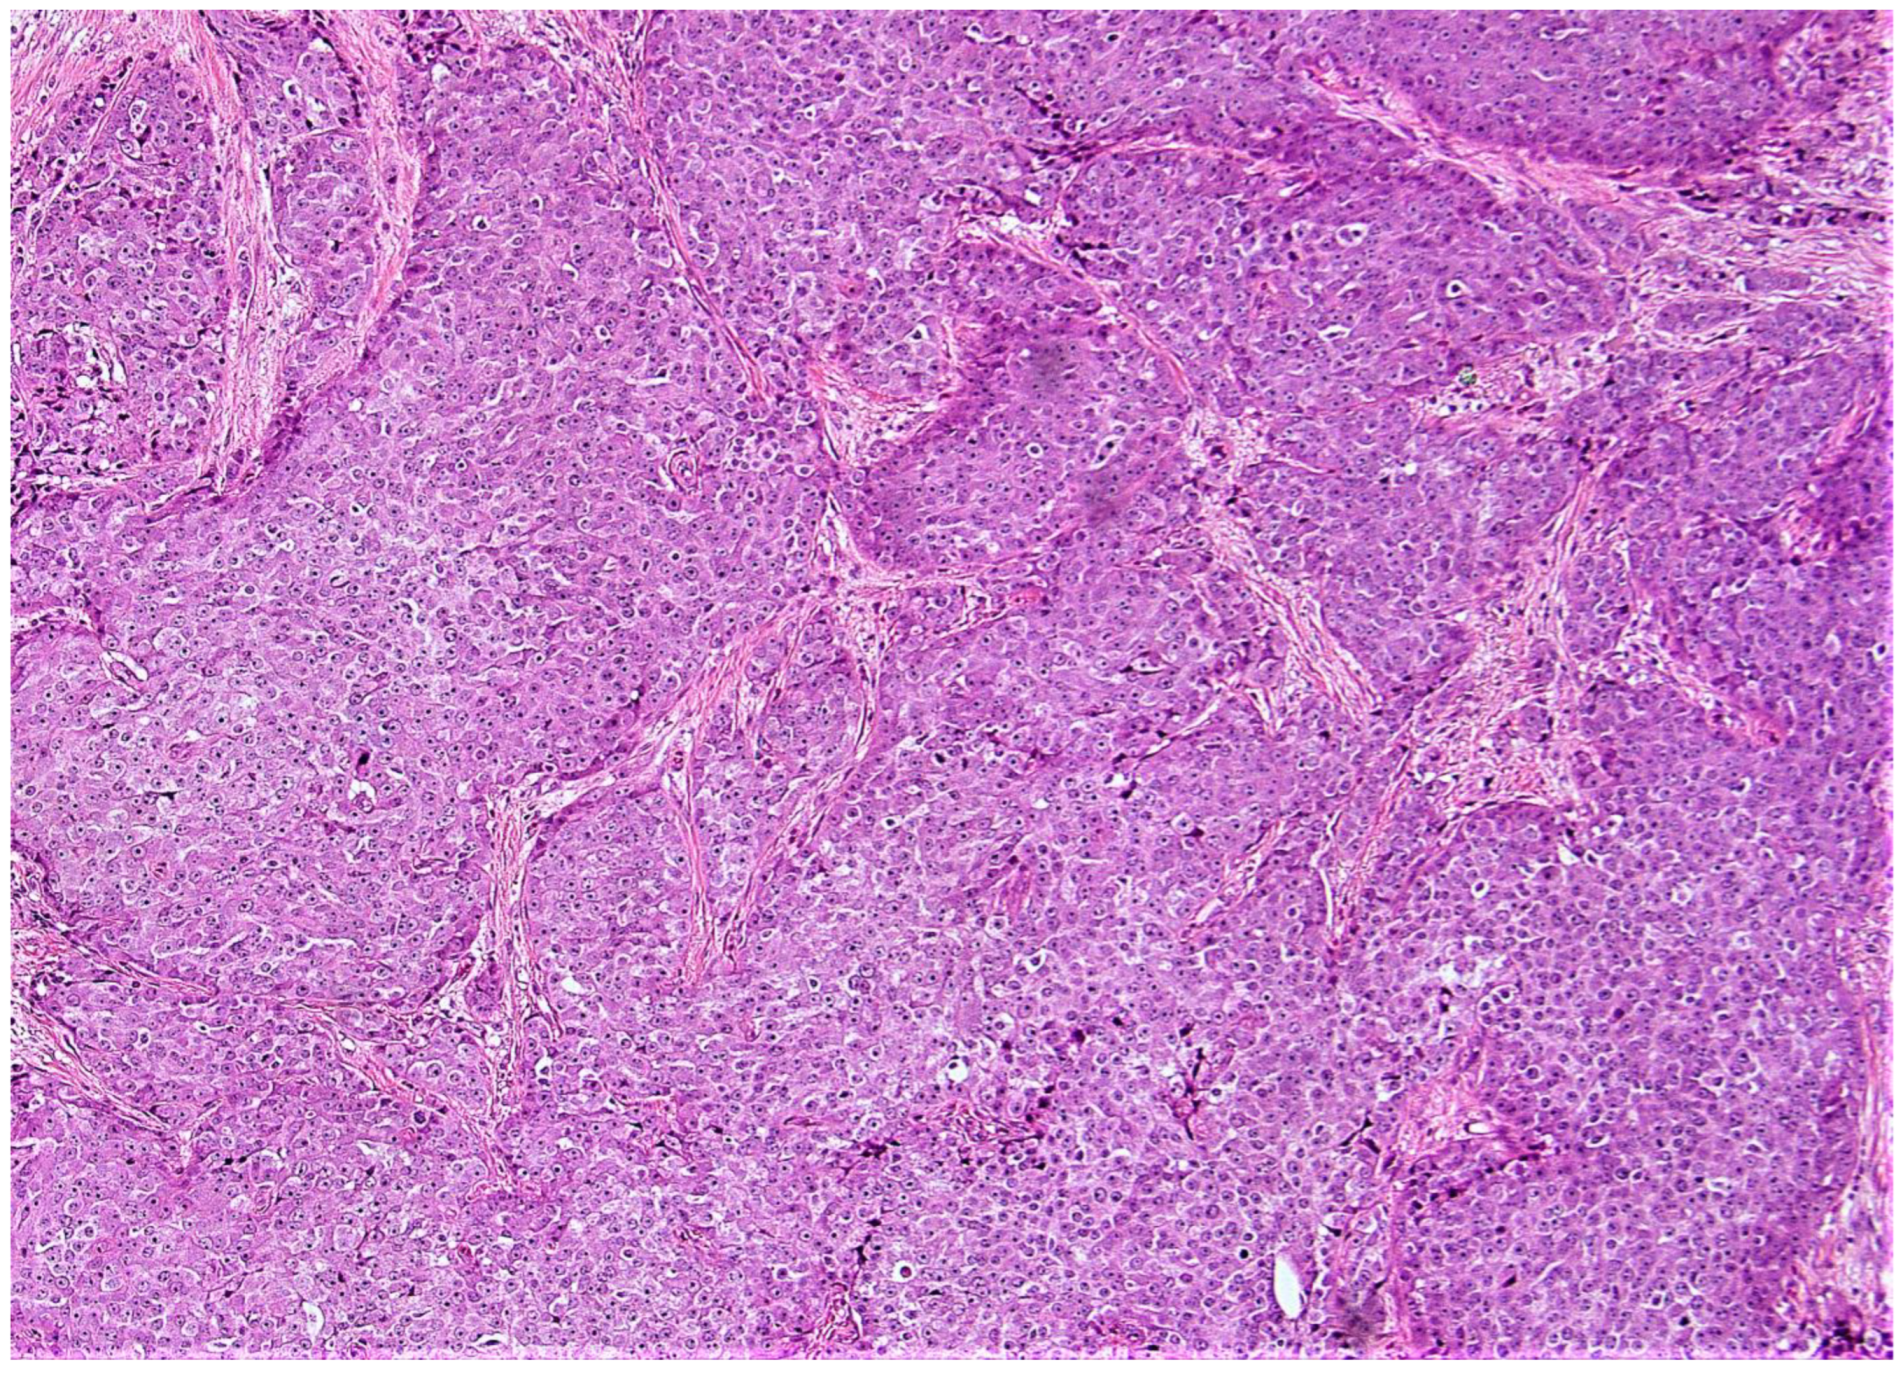

Figure 3.

(A,B) (10×): Two examples of very low risk aMMs patients considered to be higher risk by ODX (A) ([Supplemental Table S1—case # 4]; (B) [Supplemental Table S1—case # 6]). Note the low grade histologic qualities in both patients. Note the background inflammation and DCIS in (A), both of which have been suggested as potential artifacts associated with an elevated ODX recurrence score [95]. Note the somewhat cellular stroma in (B), which has also been associated with an elevated ODX recurrence score [95]. Neither of these patients recurred (follow-up of 98 and 137 months, respectively).

(A,B) (10×): The two low risk aMMs patients considered to be high risk by ODX with a breast cancer recurrence (A) ([Supplemental Table S2—case # 1]; (B) [Supplemental Table S2—case # 2]). Note the lower grade (A) to intermediate grade (B) histologic qualities in both patients. As in (A) and (B), note the background inflammation in (A), and the somewhat cellular stroma in (B), both of which have been associated with an elevated ODX recurrence score [95].